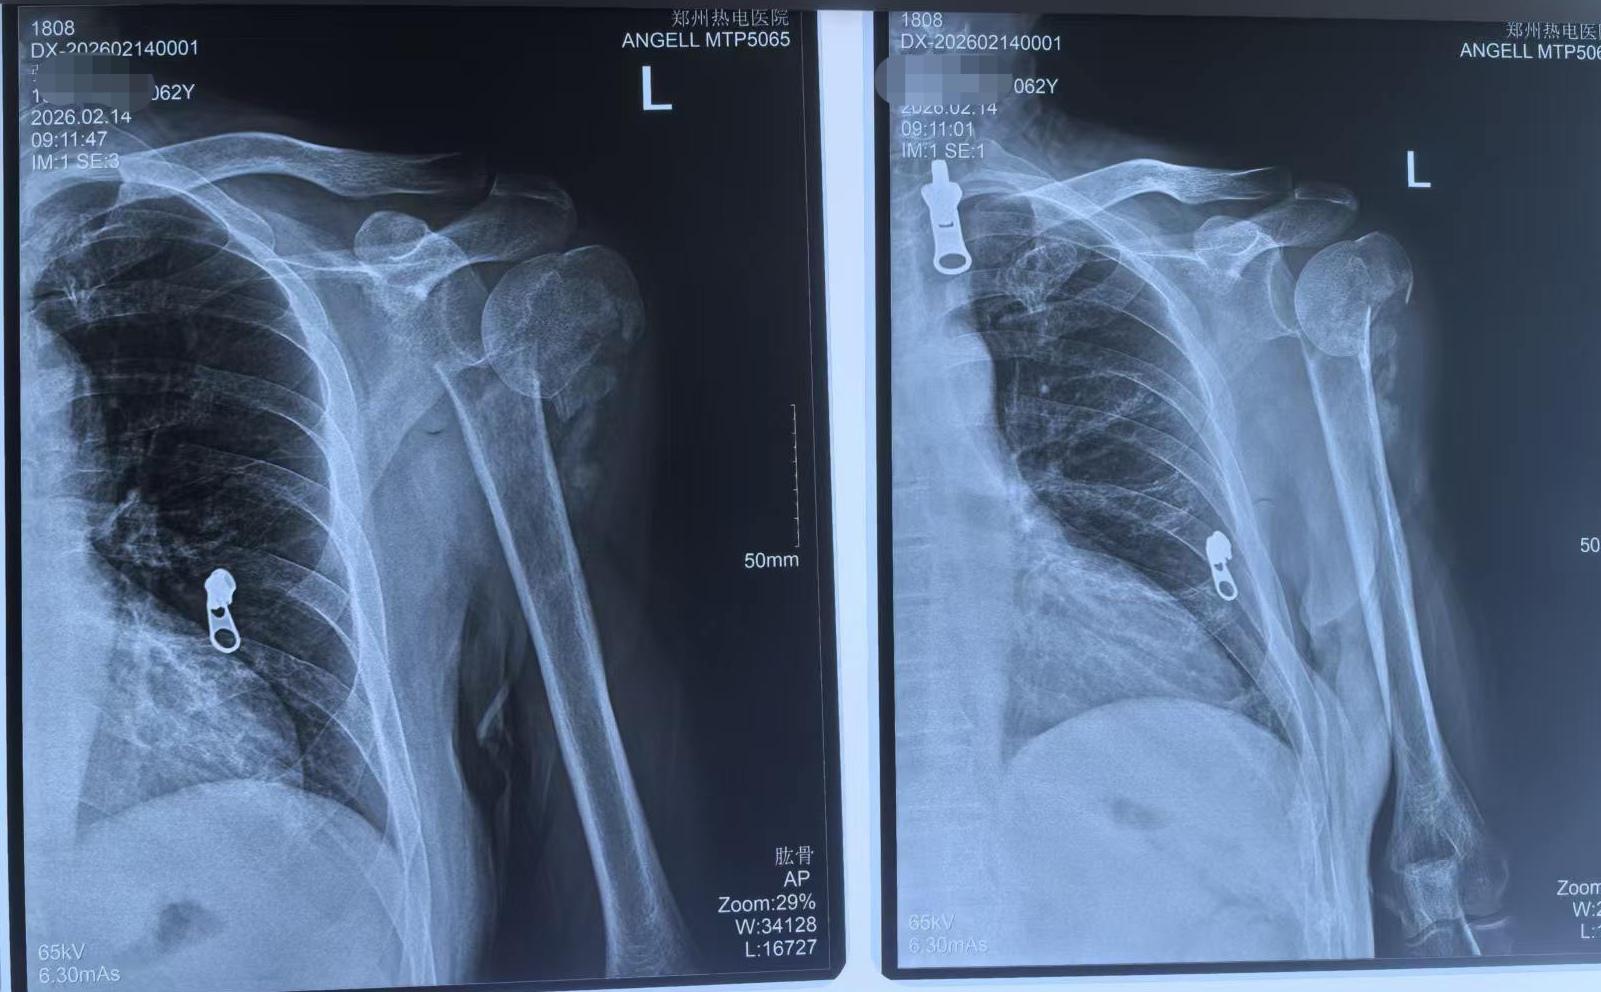

反肩关节置换。陈旧性肱骨近端粉碎骨折,RTSA完美解决。